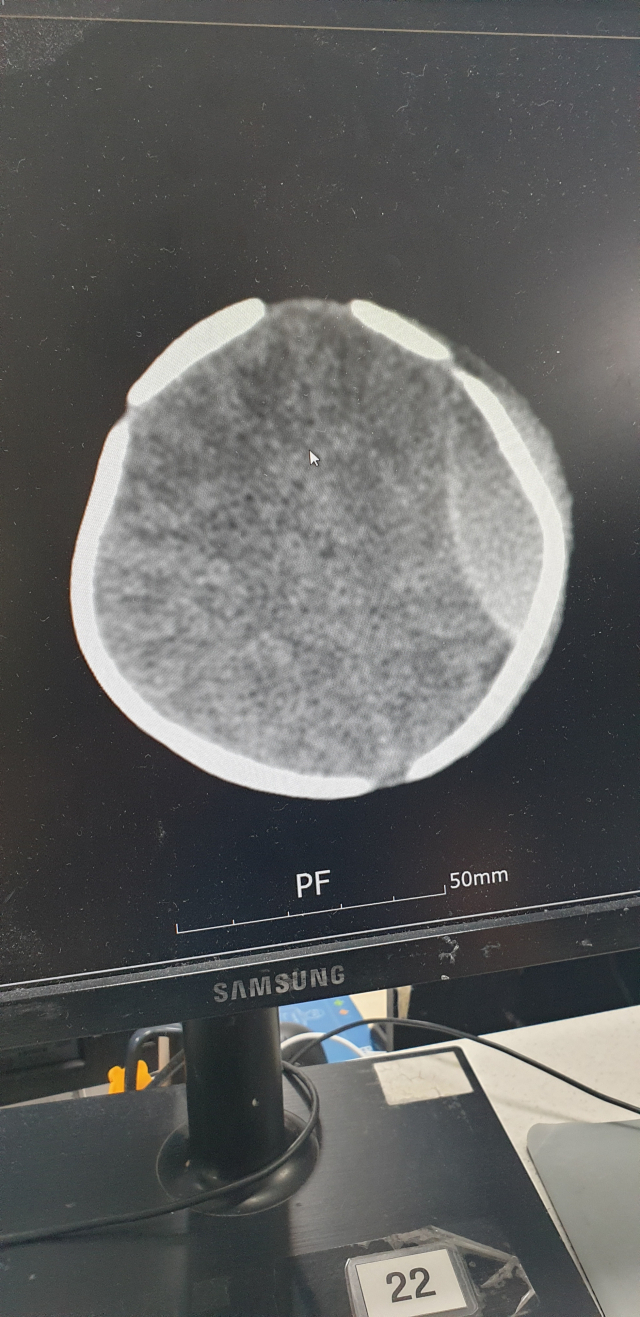

검찰이 생후 13일 아기를 처치대에서 떨어뜨려 다치게 한 혐의로 산후조리원 관계자들을 기소했다. 사진은 낙상 피해 아기 머리 CT 사진. 낙상 피해 부모 측 제공 검찰이 생후 13일 아기를 처치대에서 떨어뜨려 다치게 한 혐의로 산후조리원 관계자들을 기소했다. 사진은 낙상 피해 아기 머리 CT 사진. 낙상 피해 부모 측 제공

생후 13일 된 아기를 처치대에서 떨어뜨려 다치게 한 혐의로 부산 사하구의 한 산후조리원 원장과 간호사 등 3명이 재판에 넘겨졌다.

이들은 지난해 11월 28일 사하구의 한 산후조리원에서 생후 13일 된 아기를 높이 85cm의 처치대에서 떨어뜨린 혐의를 받는다. 사건 당시 이 아기를 돌보던 간호조무사는 자리를 비웠고, 그 사이 처치대 위에 혼자 있던 아기가 아래로 떨어졌다.

조리원은 사고 하루 뒤인 29일 엑스레이 검사 결과 골절상 등을 확인해 그제서야 부모에게 사고 사실을 알렸다. 아기는 뒤늦게 대학병원으로 옮겨져 수술을 받았고, 건강을 회복해 퇴원했다. 하지만 아기가 너무 어린 탓에 5살 때까지 추적 검사를 통해 지적 능력 등을 지켜봐야 한다.